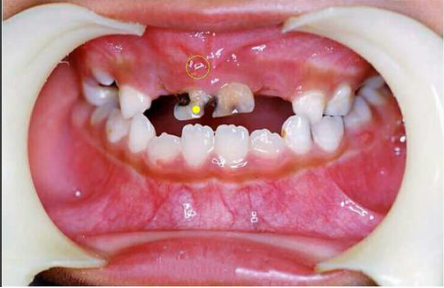

2. 导致根尖周病变:乳牙严重龋坏的时候会导致根尖周病变,会使患牙的牙根暴露于牙龈表面,有的家长还误以为是牙龈上长新牙。

0913325456-3.png

3. 影响恒牙发展:乳牙长期慢性的根尖周炎症,会侵犯下方的恒牙胚,造成继承恒牙釉质形成障碍或发育不良,严重的还可使恒牙胚发育中断,形成囊肿,导致恒牙不能正常萌出。